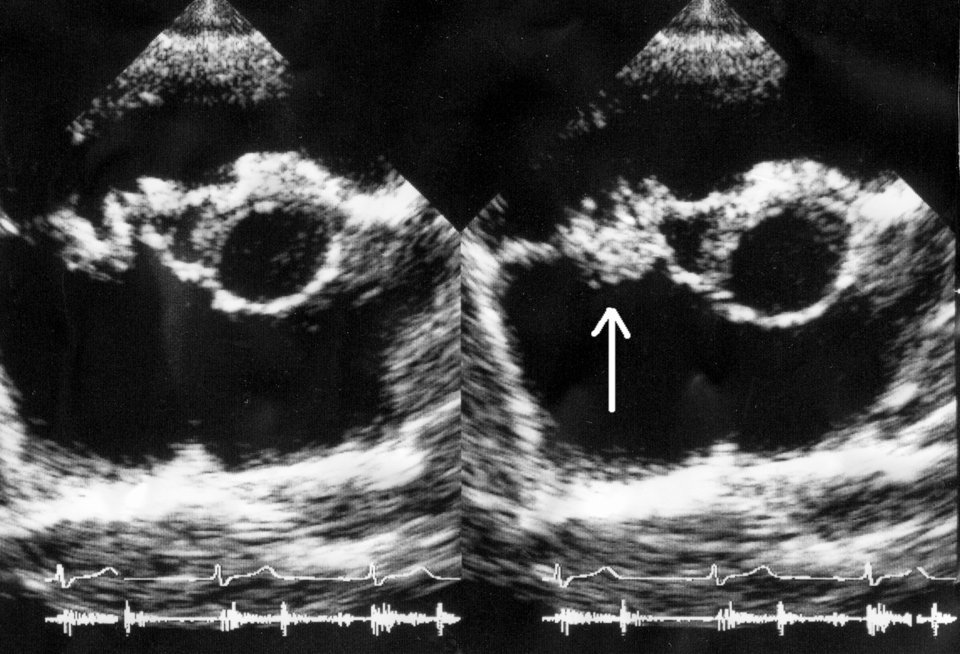

© Daisuke Koya et al/Wikipedia © Daisuke Koya et al/Wikipedia